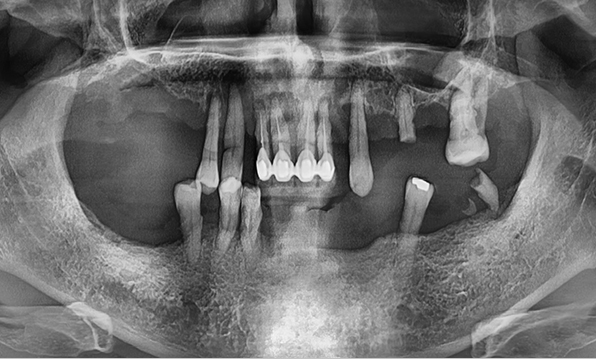

Case 01

Before After